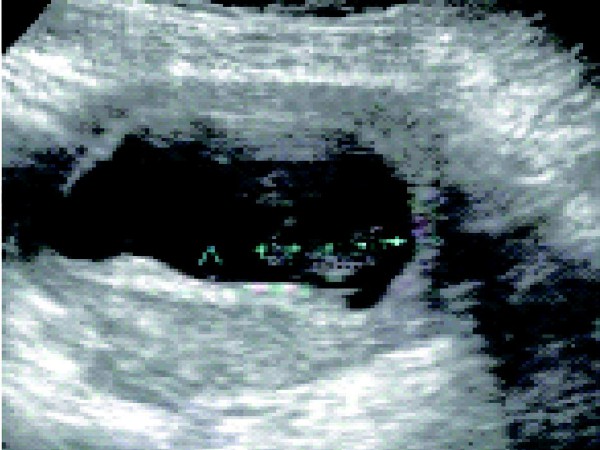

患者,女,30 岁。停经54 天,尿HCG(+),不规则阴道流血一周,加剧一天。经腹部超声显示:子宫腔内可见胚囊,胚囊内可见胚芽;宫腔下段胚囊与子宫肌层之间可见不规则低回声区,为宫腔积血;宫颈内口闭合。

超声诊断:宫内早孕,伴宫腔积血,先兆流产可能。